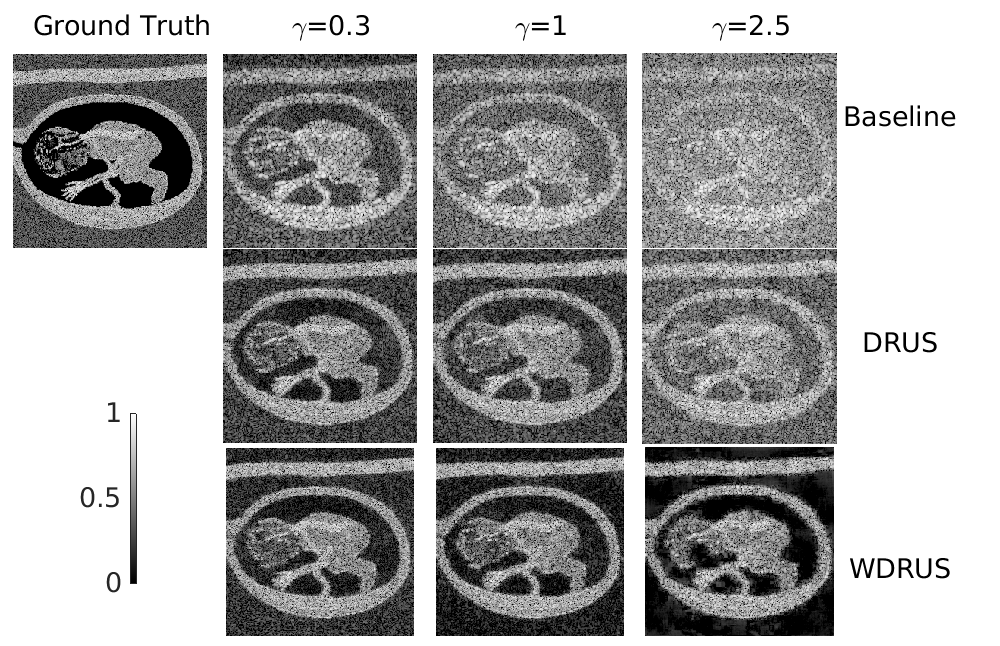

We simulate data from two phantoms, a synthetic SynVitro and Field II fetus [12, 13]. The model matrix 𝐇𝐇{\mathbf{H}} includes receive apodization using Hann window and f-number=0.5absent0.5=0.5, and the beamformer 𝐁=𝐇t𝐁superscript𝐇𝑡\mathbf{B}=\mathbf{H}^{t}. We simulated channel data 𝐲=𝐇𝐱+𝐧𝐲𝐇𝐱𝐧\mathbf{y}=\mathbf{Hx}+\mathbf{n} with six levels of additive noise (γ=0.3,0.7,1.0,1.5,2.0,2.5𝛾0.30.71.01.52.02.5\gamma=0.3,0.7,1.0,1.5,2.0,2.5).

both measured on the four anechoic regions, where the subscripts ‘in’ and ‘out’ indicate inside or outside the target regions, v𝑣v denotes the pixel values, and f𝑓f refers to the histograms of pixels in each region. The restored images and metrics are summarized in Fig. 2. The metrics for SynVitro are averaged over the different noise levels for simplicity.

Qualitatively and quantitatively, both DRUS and WDRUS significantly outperform the matched-filtering baseline 𝐇t𝐲superscript𝐇𝑡𝐲{\mathbf{H}}^{t}{\mathbf{y}}, and WDRUS is generally superior to DRUS in terms of noise reduction and contrast enhancement. The two proposed approaches even outperform the ground truth for resolution at low-noise conditions (e.g. γ=0.3,0.7,1.0𝛾0.30.71.0\gamma=0.3,0.7,1.0), while the resolution of images restored by WDRUS under high-noise conditions (e.g. γ=1.5,2.0,2.5𝛾1.52.02.5\gamma=1.5,2.0,2.5) is worse than that of DRUS.

(b) fetus phantom.

Figure 2: Comparison of restored images on synthetic data. it=50it50\texttt{it}=50 for DRUS and WDRUS. All images are in decibels with a dynamic range [-60,0]. The fetus images are normalized between 0 to 1 for calculating the SSIM and PSNR.